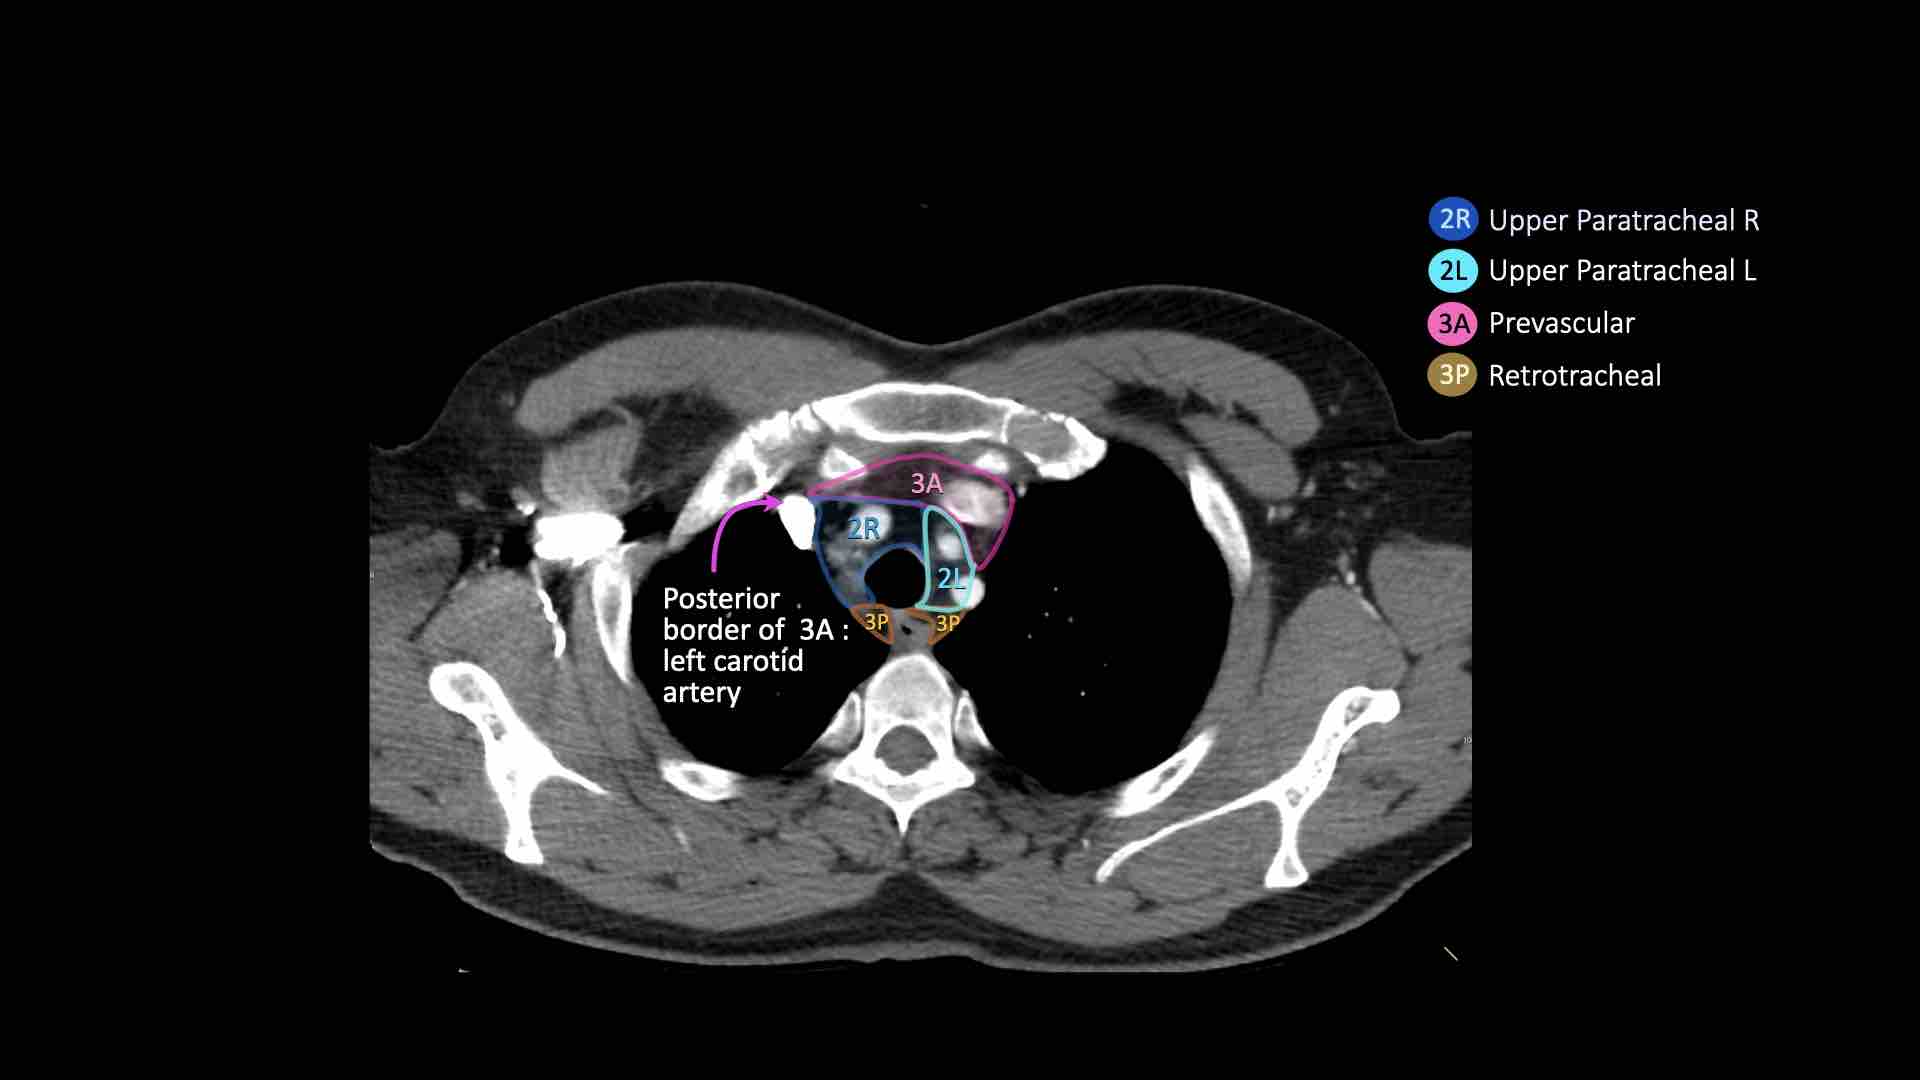

3A.Trước mạch máu

Các hạch này không tiếp giáp với khí quản như các hạch ở nhóm 2, mà nằm ở phía trước các mạch máu.

3. Hạch trước mạch máu và trước cột sống

Hạch nhóm 3 không nằm kề khí quản như hạch nhóm 2.

Chúng có thể là:

3A nằm phía trước các mạch máu, hoặc

3B nằm phía sau thực quản, vốn nằm ở vị trí trước cột sống.

Hạch nhóm 3 không thể tiếp cận bằng nội soi trung thất.

Hạch 3P có thể tiếp cận bằng siêu âm nội soi (EUS).

Bên trái là hạch 3A nằm trong khoang trước mạch máu.

Lưu ý cũng có các hạch cạnh khí quản dưới bên phải, tức là hạch nhóm 4R.